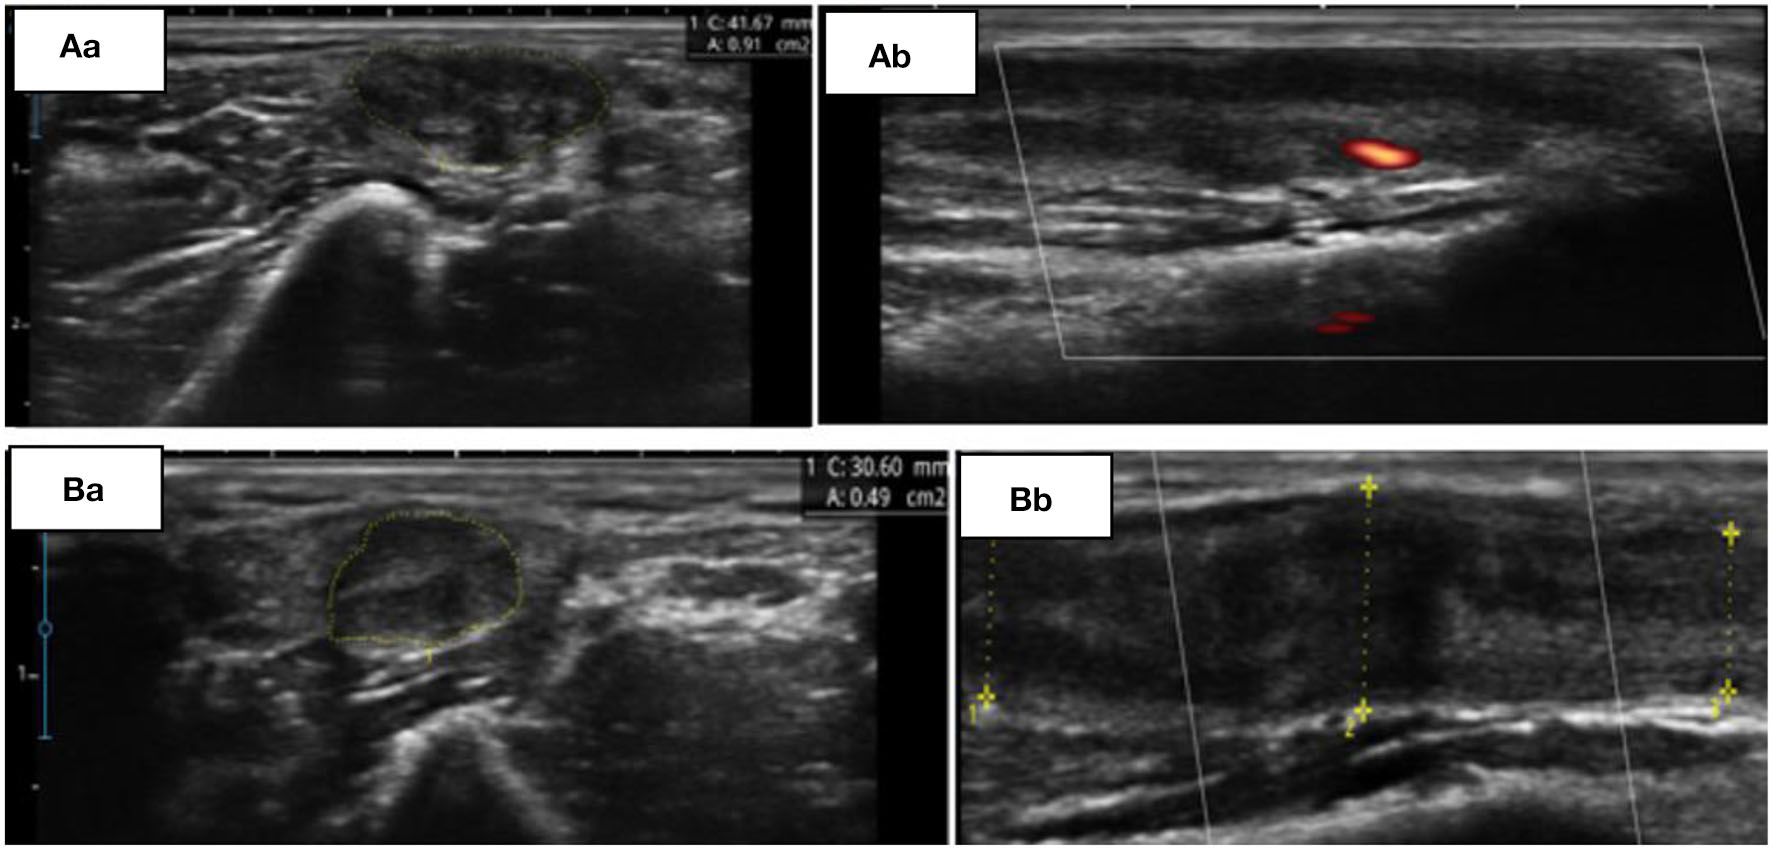

The patient was followed up in neurological appointments every 2 weeks, and after 2 months, the patient was reassessed and there was no complaint of paresthesia or pain upon neurological examination, an MRC grade 5 was determined in all muscles, and a subjective reduction in neural thickening was noted. An NCS was repeated within 3 months after the start of corticosteroid therapy and an improvement in electrophysiological values was observed (Table 1). NMUS showed an improvement in echogenicity and fascicular disarray, a 50% reduction in the cross-sectional diameter at the two levels described above, and no flow in the Power Doppler (Figure 1).

Figure 1

(A) Initial findings from ultrasonography (USG). Transverse (Aa) and longitudinal (Ab) view of the left ulnar nerve at the supraepicondylar region. (B) Control USG, 60 days later. Transverse (Ba) and longitudinal (Bb) view of the same nerve at the supraepicondylar region.